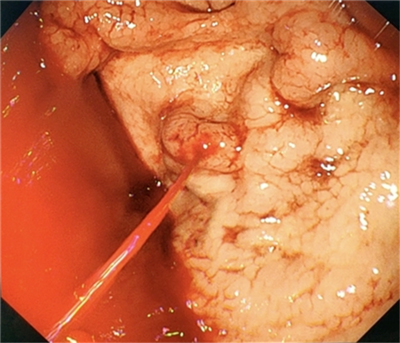

喷射状出血

组织胶封堵

术后创面

“患者病情凶险,血红蛋白仅65g/L,命悬一线” 患者某某,男性,46岁,有多年酒精性肝硬化失代偿期病史,此次因“呕血、黑便”入院,病情十分危急,血红蛋白低至65g/L(仅为正常值的1/2),生命体征极不稳定,随时可能因失血性休克而危及生命,随后转入重症监护室,重症医学科团队立即给予输血、补液、升压等抢救措施,稳定生命体征。 “内镜下精准止血,硬化和组织胶联合封堵出血血管" 面对如此凶险的病情,消化内科团队迅速启动应急抢救流程。术中可见,患者的胃底静脉曲张破裂,呈喷射状出血,情况万分危急!在执行主任詹原泉教授的指导下,曾璐副主任医师凭借丰富的手术经验,立即为患者实施内镜下胃底静脉曲张硬化剂注射+组织胶封堵术。术中即刻止血,患者转危为安! 后患者好转出院,此次手术的成功,不仅体现了我院消化内科在危急重症救治方面的强大实力。未来,我院将继续提升技术水平,为更多消化道出血患者提供救治服务! (图片来源于网络) 肝硬化导致的食管胃底静脉曲张破裂出血是消化科最凶险的急症之一(见上图清晰图片),传统药物治疗效果有限,外科手术风险极高。而内镜下止血(硬化剂/组织胶/套扎)是目前国际公认的首选治疗方案,但对操作医生的技术要求极高。 专家提醒 肝硬化患者一旦出现呕血、黑便等症状,需立即就医。内镜下止血是治疗食管胃底静脉曲张破裂出血的首选方法,但需在具备条件的医院由经验丰富的团队实施。